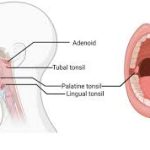

Östaki borusu, burun ve orta kulak arasında yer alan bir kanaldır ve orta kulağın havalanmasını, basınç dengelenmesini ve salgıların drenajını sağlar.

Adenoid dokusu nasofarenkste, Östaki borusunun açıldığı bölgeye yakın bulunur.

Östaki borusunun farengeal açıklığı direkt olarak mekanik olarak tıkanır.

Eustachian Tube Dysfunction in Children With Adenoid Hypertrophy – Adenoid hipertrofisi çocuklarda Östaki tüp disfonksiyonuna (ETD) sık yol açtığını ve adenoidektominin orta kulak ventilasyonunu iyileştirebildiğini gösteren klinik çalışma.

Adenotonsiller Hipertrofinin Effüzyonlu Otitis Media Üzerine Etkileri – Adenoid hipertrofisinin Östaki tüpü tıkanıklığı ile fonksiyon bozukluğuna ve sonuçta orta kulakta effüzyonlara neden olduğunu kabul eden bilimsel makale.